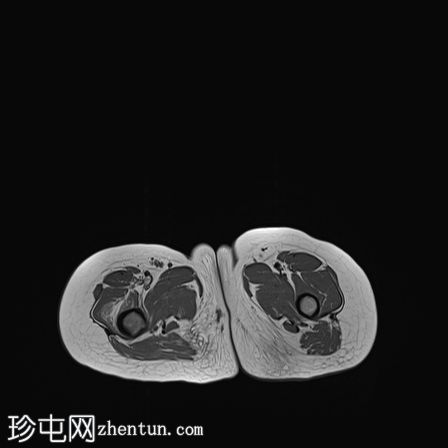

髋部

MRI

冠状位

T1

轴向

轴向PD

脂肪饱和度

轴向T1

C+脂肪饱和度

右上股骨大转子正下方外侧皮质区可见一小的皮质基部病变,边缘呈低信号,大小约为0.7 x 0.7厘米。

邻近的股骨近端骨干和股骨颈有水肿。

水肿有扩散至邻近肌肉的迹象。